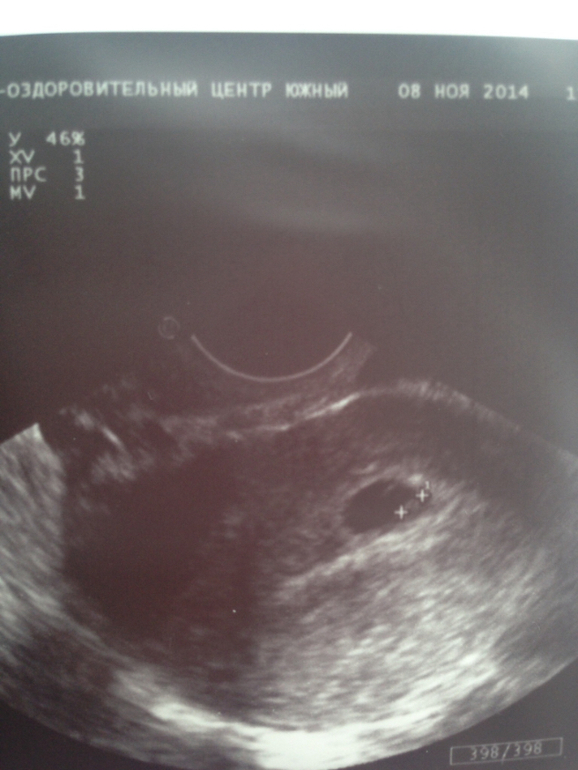

1 узи это 08.11 второе узи сегодняшнее

11.11.14 были на узи. Все хорошо сердцебиение есть, поставили 5 нед. 2 дня. Прогрессирующая. Сегодня была на узи, так как вчера немного закровило, точнее более сукровично кровянистые выделения. В общем, сердцебиения врач не нашла и сказала, что эмбрион какой то приплюснутый скорее всего он остановился в развитии. В общем не сил ни эмоций уже нет. Мы столько радовались с мужем, что спустя 3 года наконец то все получилось. Тем более, что до этого у меня тоже была замершая. Я уже не знаю что делать. У меня просто истерика.

Вы после первой замершей лечили что-то или все хорошо было, матку смотрели очагов эндометрита не было? что-то ведь не нравится эмбриону, в 5-6 недель сердцебиение можно как раз услышать у меня в 5 недель 6 дней было все, два года назад была замершая -ничего не видели, снимок как у Вас второй, Вы, конечно, перепроверьте в другом месте еще